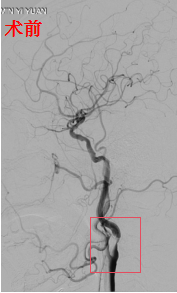

66岁男性,因"突发右上肢无力2天"入院,诊断为左侧内分水岭性脑梗死、左侧颈动脉重度狭窄。经介入团队全面评估,医患充分沟通后,实施了颈动脉支架植入术:手术过程顺利,支架精准置入,血流恢复通畅。

然而,就在手术结束的那一刻,术者敏锐地发现患者右上肢肌力突然由术前的3级(可抬离床面)降至0级(完全瘫痪)。虽然患者神志清楚、言语流利,但这一细微变化立即触发了抢救应急预案,复查头部CT显示:左侧额顶叶梗死区域出现脑出血转化——这正是高灌注综合征的典型表现!